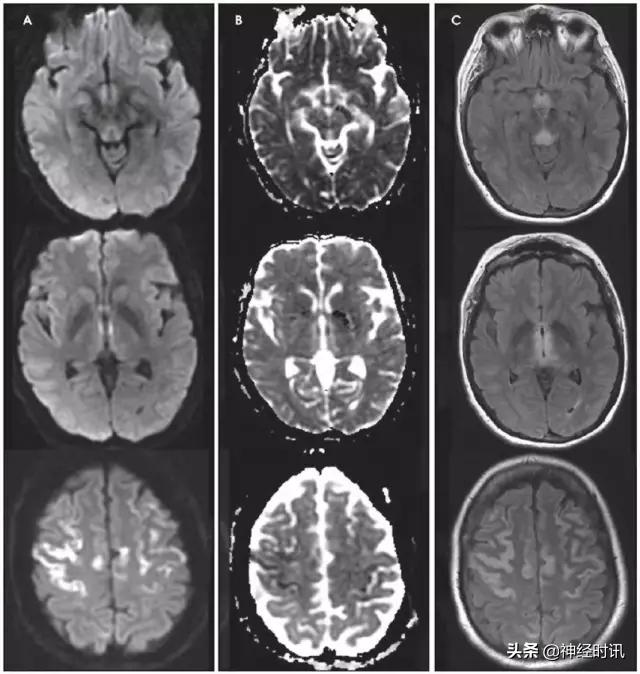

癫 痫

三分之一的卒中类似疾病是由于癫痫发作或发作后功能障碍导致。有时癫痫也可导致弥散受限(图2)。其分布特点不符合血管分布,水肿和脑回增强出现更早,脑灌注正常或增加,无血管闭塞,有时同时有皮层弥散受限和皮层下弥散增加。

图2 一例66岁男性,癫痫发作伴意识状态改变、急性失语和右侧凝视,拟诊脑卒中并给予IV-tPA治疗。左侧病灶情况下的右侧凝视可提示癫痫发作。他的入院MRI显示左侧额顶叶皮层和皮层下白质弥散受限(A和B)和水肿(C)。他的症状和影像学(图像未提供)显示在出院前完全缓解。